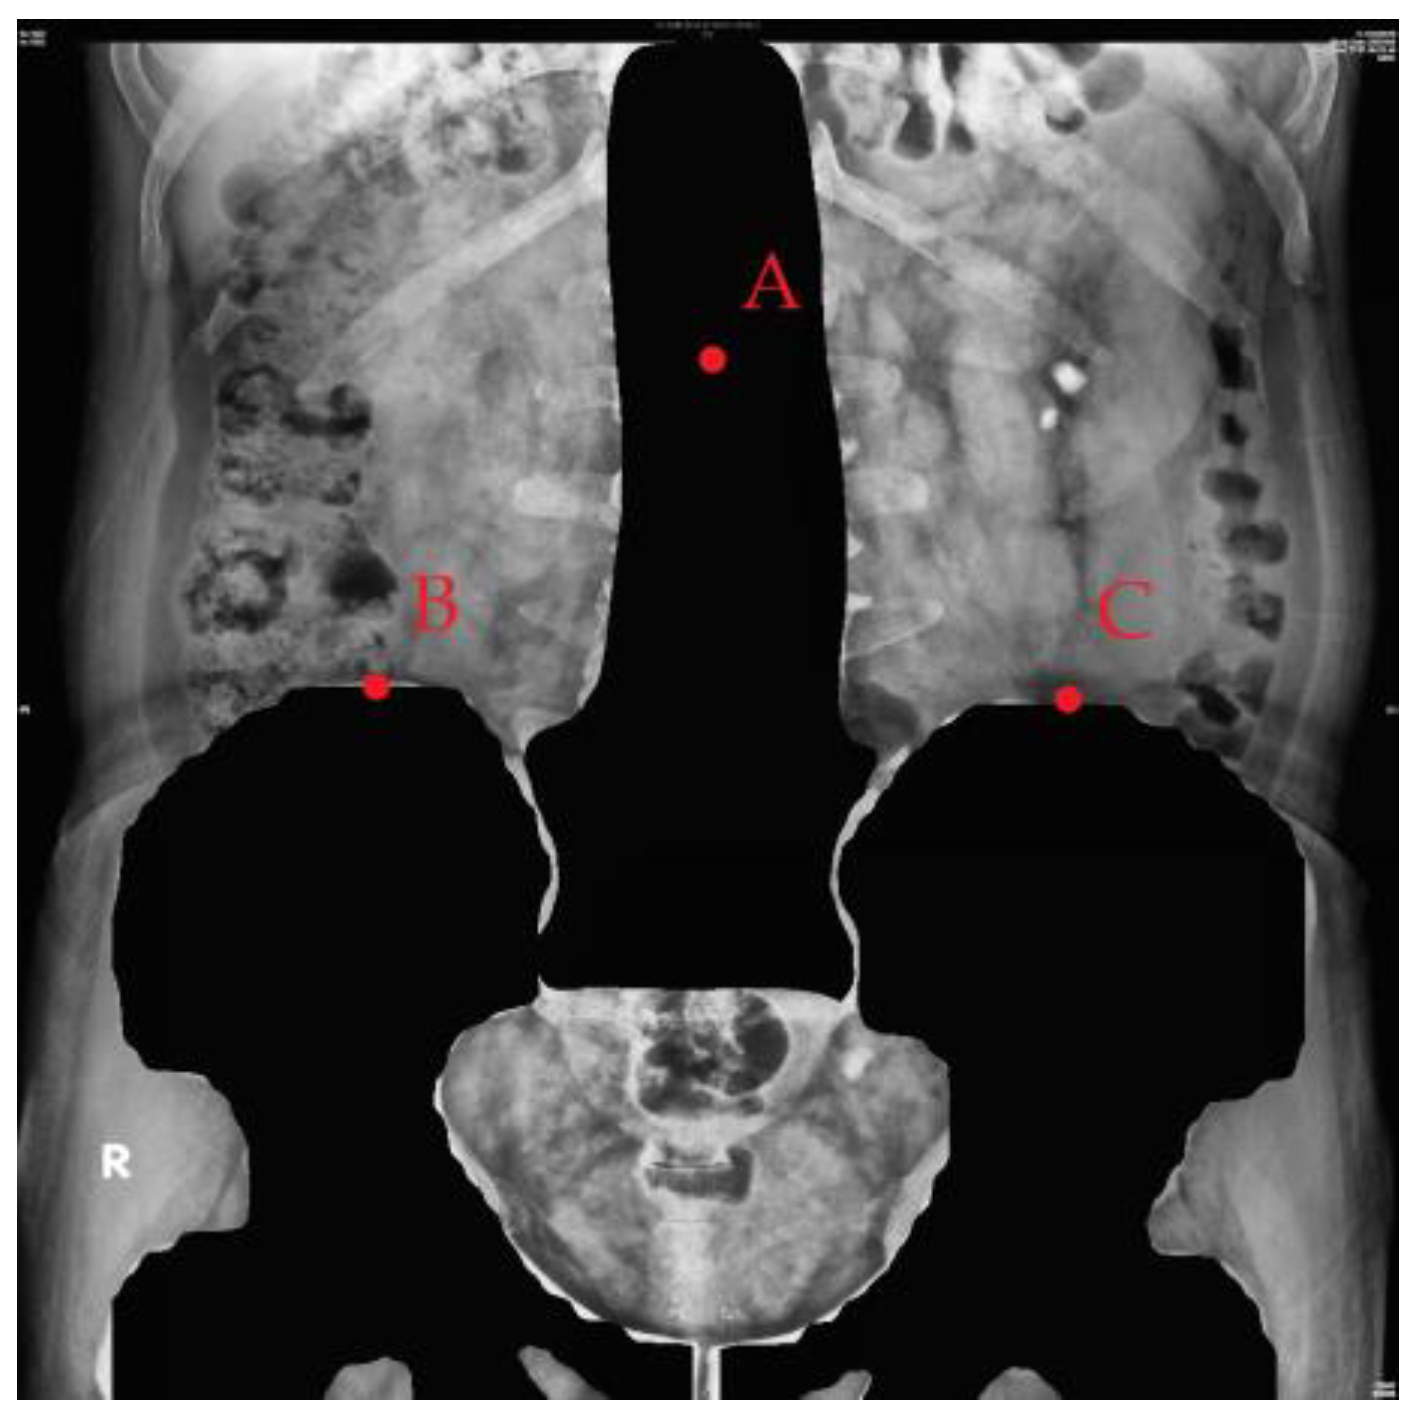

2.3. Image Preprocessing

2.3.2. Image Mask

2.3.3. Image Cropping